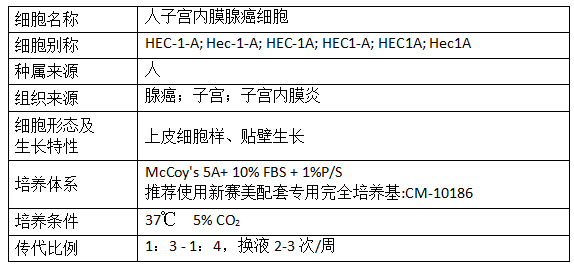

产品信息: